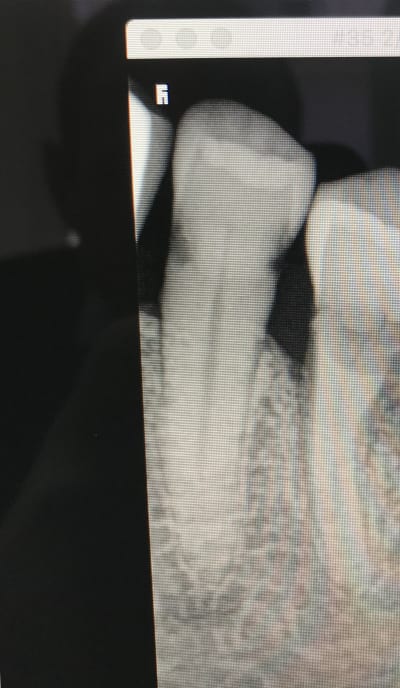

Je commencerais par la 36.

Pour la 35 c'est jouable avec les matrices adhoc etre sous gingival n'est pas un souci. . Mais attention au sensiblités post op bien prévenir le patient avant pour éviter les remarques du genre " j'avais pas mal avant et j'ai mal après".

Merci pour vos réponses. Chicot, tu attaques les lésions par voie occlusale.... Sacré délabrement ? et c'est très infra... pour la 36, il y a un gros compo de collet, mais la lésion s'étend désormais en distale... Idem, je suis tiraillé par la couronne...

C'est plus confortable un onlay en sous gingival of course,. Donc remontée de marche en compo avec matrice adhoc et ensuite quel délabrement justifie l'onlay il y a simplement 2 box proximaux à faire.